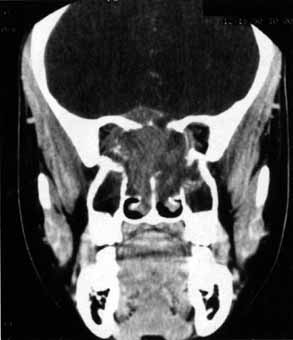

CASE 1 A 70-year-old woman presented with a 6-month history of progressive diplopia and ptosis. She demonstrated complete right third, fourth, and sixth cranial nerve palsies, and hypesthesia of cranial nerve V1 (Fig. 22A). The right pupil was dilated. Computed tomography (CT) disclosed an intracavernous aneurysm (see Fig. 22B). The so-called superior orbital fissure syndrome occurs when an infiltrative, inflammatory, or ischemic event occurs within the superior orbital fissure, but not in the orbital apex.4 A complete superior orbital fissure syndrome occurs when all the neurovascular components passing through the superior orbital fissure are damaged, producing a total ophthalmoplegia, ptosis, and anesthesia of cranial nerve V1 (see Fig. 22A). The pupil may be dilated, miotic, or midposition and fixed, depending on the balance of parasympathetic and sympathetic damage. The superior ophthalmic vein, best seen on CT, may be dilated if venous outflow from the orbit is obstructed. Clues to venous outflow obstruction are increased intraocular pressure, fullness of the upper eyelid, and hyperemia of the deep Tenon's vessels. Ophthalmoscopically, the retinal veins may be dilated. The effect of a lesion in the superior orbital fissure or the anterior cavernous sinus cannot be differentiated clinically (see Fig. 22B). When the posterior cavernous sinus becomes involved, hypesthesia of cranial nerve V2 may also be present. The only difference between a superior orbital fissure syndrome and an orbital apex syndrome is the presence of visual loss caused by optic nerve involvement. Visual acuity, color vision, or the visual field are abnormal. An ipsilateral relative afferent pupil defect is present. CASE 2 A 30-year-old man noted diplopia and right ptosis for the past month. The patient demonstrated normal vision and symmetric pupils but had a neurogenic ptosis (Fig. 23A) and limited right supraduction (Fig. 23B). Otherwise his extraocular movements were full. CT demonstrated an intracranial aneurysm of the posterior communicating artery aneurysm (Fig. 23C). Anatomically, the third cranial nerve branches into its superior and inferior divisions as it enters the orbit through the superior orbital fissure. Superior branch damage results in ptosis (levator muscle) and decreased supraduction (superior rectus muscle). Inferior branch damage results in decreased adduction (medial rectus), decreased infraduction (inferior rectus), decreased excycloduction (inferior oblique), and a dilated pupil (parasympathetic). Anatomically, a cranial nerve III branch nerve lesion seems to imply an anterior cavernous sinus or orbital apex localization. However, functionally, the third cranial nerve may bifurcate in the intracranial portion of the nerve, so cranial nerve III branch nerve palsies have been demonstrated with intracranial lesions. The localizing finding of a cranial nerve III branch nerve lesion is therefore not absolute (see Fig. 23).46 CASE 3 A 12-year-old child was referred by his school nurse because he had been complaining intermittently of double vision and the nurse had noted intermittent right ptosis. The child presented with a right ptosis and limited infraduction of the left eye (Fig. 24A). The ptosis worsened with prolonged up-gaze. A Cogan lid twitch was noted on the right with upward saccades. Injection of 1 mg of edrophonium resulted in complete resolution of diplopia and ptosis (Fig. 24B). The diagnosis was myasthenia gravis. Most orbital and cavernous sinus lesions produce afferent and efferent palsies in an anatomic pattern, for example, the superior orbital fissure has cranial nerves III, IV, VI and V1. When the pareses are not localized anatomically, or when there is variability in findings over time, one should include carcinomatosis or myasthenia gravis (see Fig. 24) in the differential diagnosis. Fatigability and a Cogan lid twitch strongly suggest myasthenia gravis. CASE 4 A 52-year-old woman presented with diplopia when looking to her right. She had noted a red right eye for the past 3 months (Fig. 25A). Visual acuity was 20/20 in both eyes and the pupils were normal. The right eye was limited in abduction. Forced duction testing showed abduction of the right eye to be restricted. Intraocular pressures were 23 mm Hg OD, and 15 mm HG OS. CT showed a dilated right superior ophthalmic vein (Fig. 25B) which was shown to be caused by a dural cavernous fistula. The right medial rectus muscle was also enlarged (Fig. 25C) because of blood engorgement, reducing muscle compliance, which accounted for the restricted abduction. Carotid cavernous fistulas can develop either as a result of trauma or spontaneously.47 A direct carotid cavernous fistula results from a tear in the intracavernous carotid artery with arteriolization of the cavernous sinus and superior orbital vein. Concomitant cranial nerve III, IV, VI, V1 and V2 paresis, elevated intraocular pressure, proptosis, and distention of the deep Tenon's vessels anteriorly (see Fig. 25A) with neuroradiologic evidence of an enlarged superior ophthalmic vein are common (see Fig. 25B). Ophthalmoplegia may also occur on a restrictive basis because of engorgement of the extraocular muscles with blood (see Fig. 25C).36 Dural carotid cavernous fistulas occur where small branches of the intracavernous carotid rupture, allowing access of arterial blood to the cavernous sinus. Typically, the findings are similar to a direct carotid cavernous fistula but of less magnitude. There is no history of trauma, and typically occurs in older persons. However, there is crossover between these two types of carotid cavernous fistula. An excessive ocular pulse tonographically may be helpful in the diagnosis of a carotid cavernous fistula in such cases.48 CASE 5 A 51-year-old woman was referred by her internist for left proptosis. The patient had noted diplopia for the past month but denied blurred vision or pain. Past history was significant for breast carcinoma requiring mastectomy. Vision was 20/20 in both eyes and the pupils were normal. Extraocular movements of the right eye were limited. Forced ductions were restricted. Exophthalmometry readings were 14 mm OD and 18 mm OS (Fig. 26A). CT disclosed a mass encircling the right globe (Fig. 26B). Biopsy disclosed metastatic scirrhous breast carcinoma retracting the right globe.